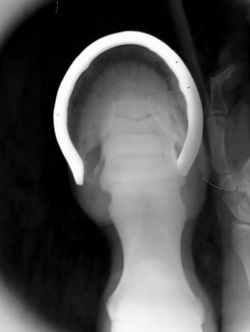

Hands in Primary Beam